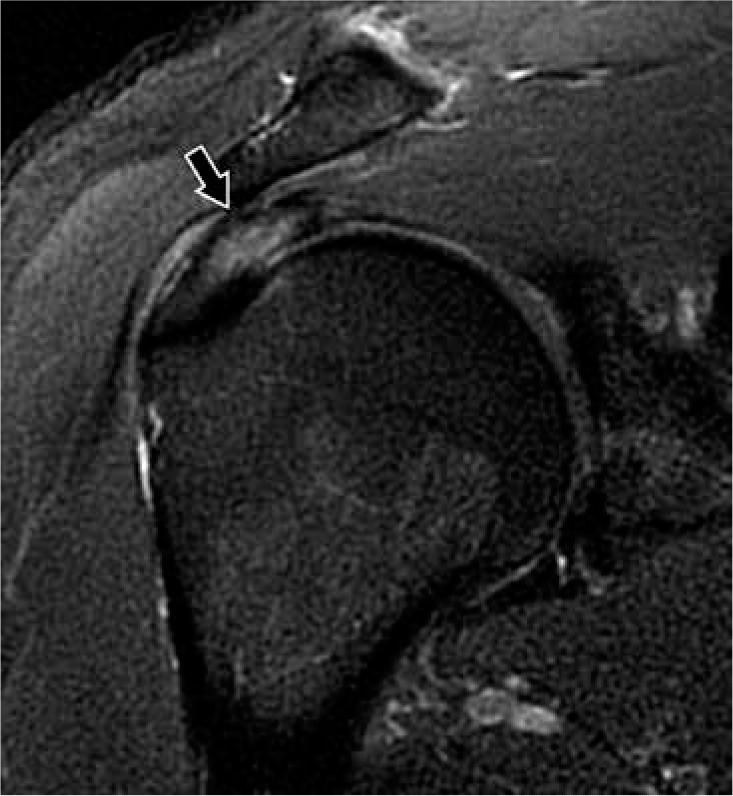

Rotator cuff tendinopathy can be classified as tendon degeneration or inflammation and is thought to be caused by intrinsic factors like tendon insult or overload, or extrinsic factors like impingement by surrounding structures. Rotator cuff tendinopathy can cause significant pain and has an incidence of 0.3-5.5% and an annual prevalence of 0.5-7.4% [17]. Signs of tendinopathy on MRI include increased signal within the tendon that has lower intensity than that of fluid on T2-weighted sequences. There may be tendon thickening, thinning, or fraying, which is the observation of a hypointense signal at the tendon margin that becomes indistinct, but there is an absence of gaps within tendon fibres (Figure 2).

Figure 2

Tendinosis in a 45-year-old man with unilateral shoulder pain. Coronal proton density-weighted, fat-suppressed magnetic resonance image shows increased signal in the superior rotator cuff (arrow) without fluid gap, consistent with tendinopathy